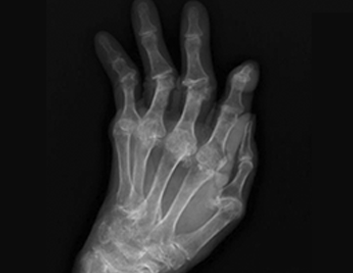

손발톱 무좀은 여러 종류의 피부사상균, 즉 곰팡이에 의해 손가락 혹은 발가락에 생기는 피부질환입니다. 원인균으로는 적색 백선균(Trichophyton rubrum)이 약 90% 정도로 흔하고 그 외에 Trichophyton mentagrophytes, Epidermophyton floccosum, Candida albicans 등이 검출되기도 합니다.

손발톱 무좀이 생기면 사진처럼 두꺼워지고 각질이 벗겨지며 간지럽고 냄새가 나고 통증을 호소하기도 합니다.